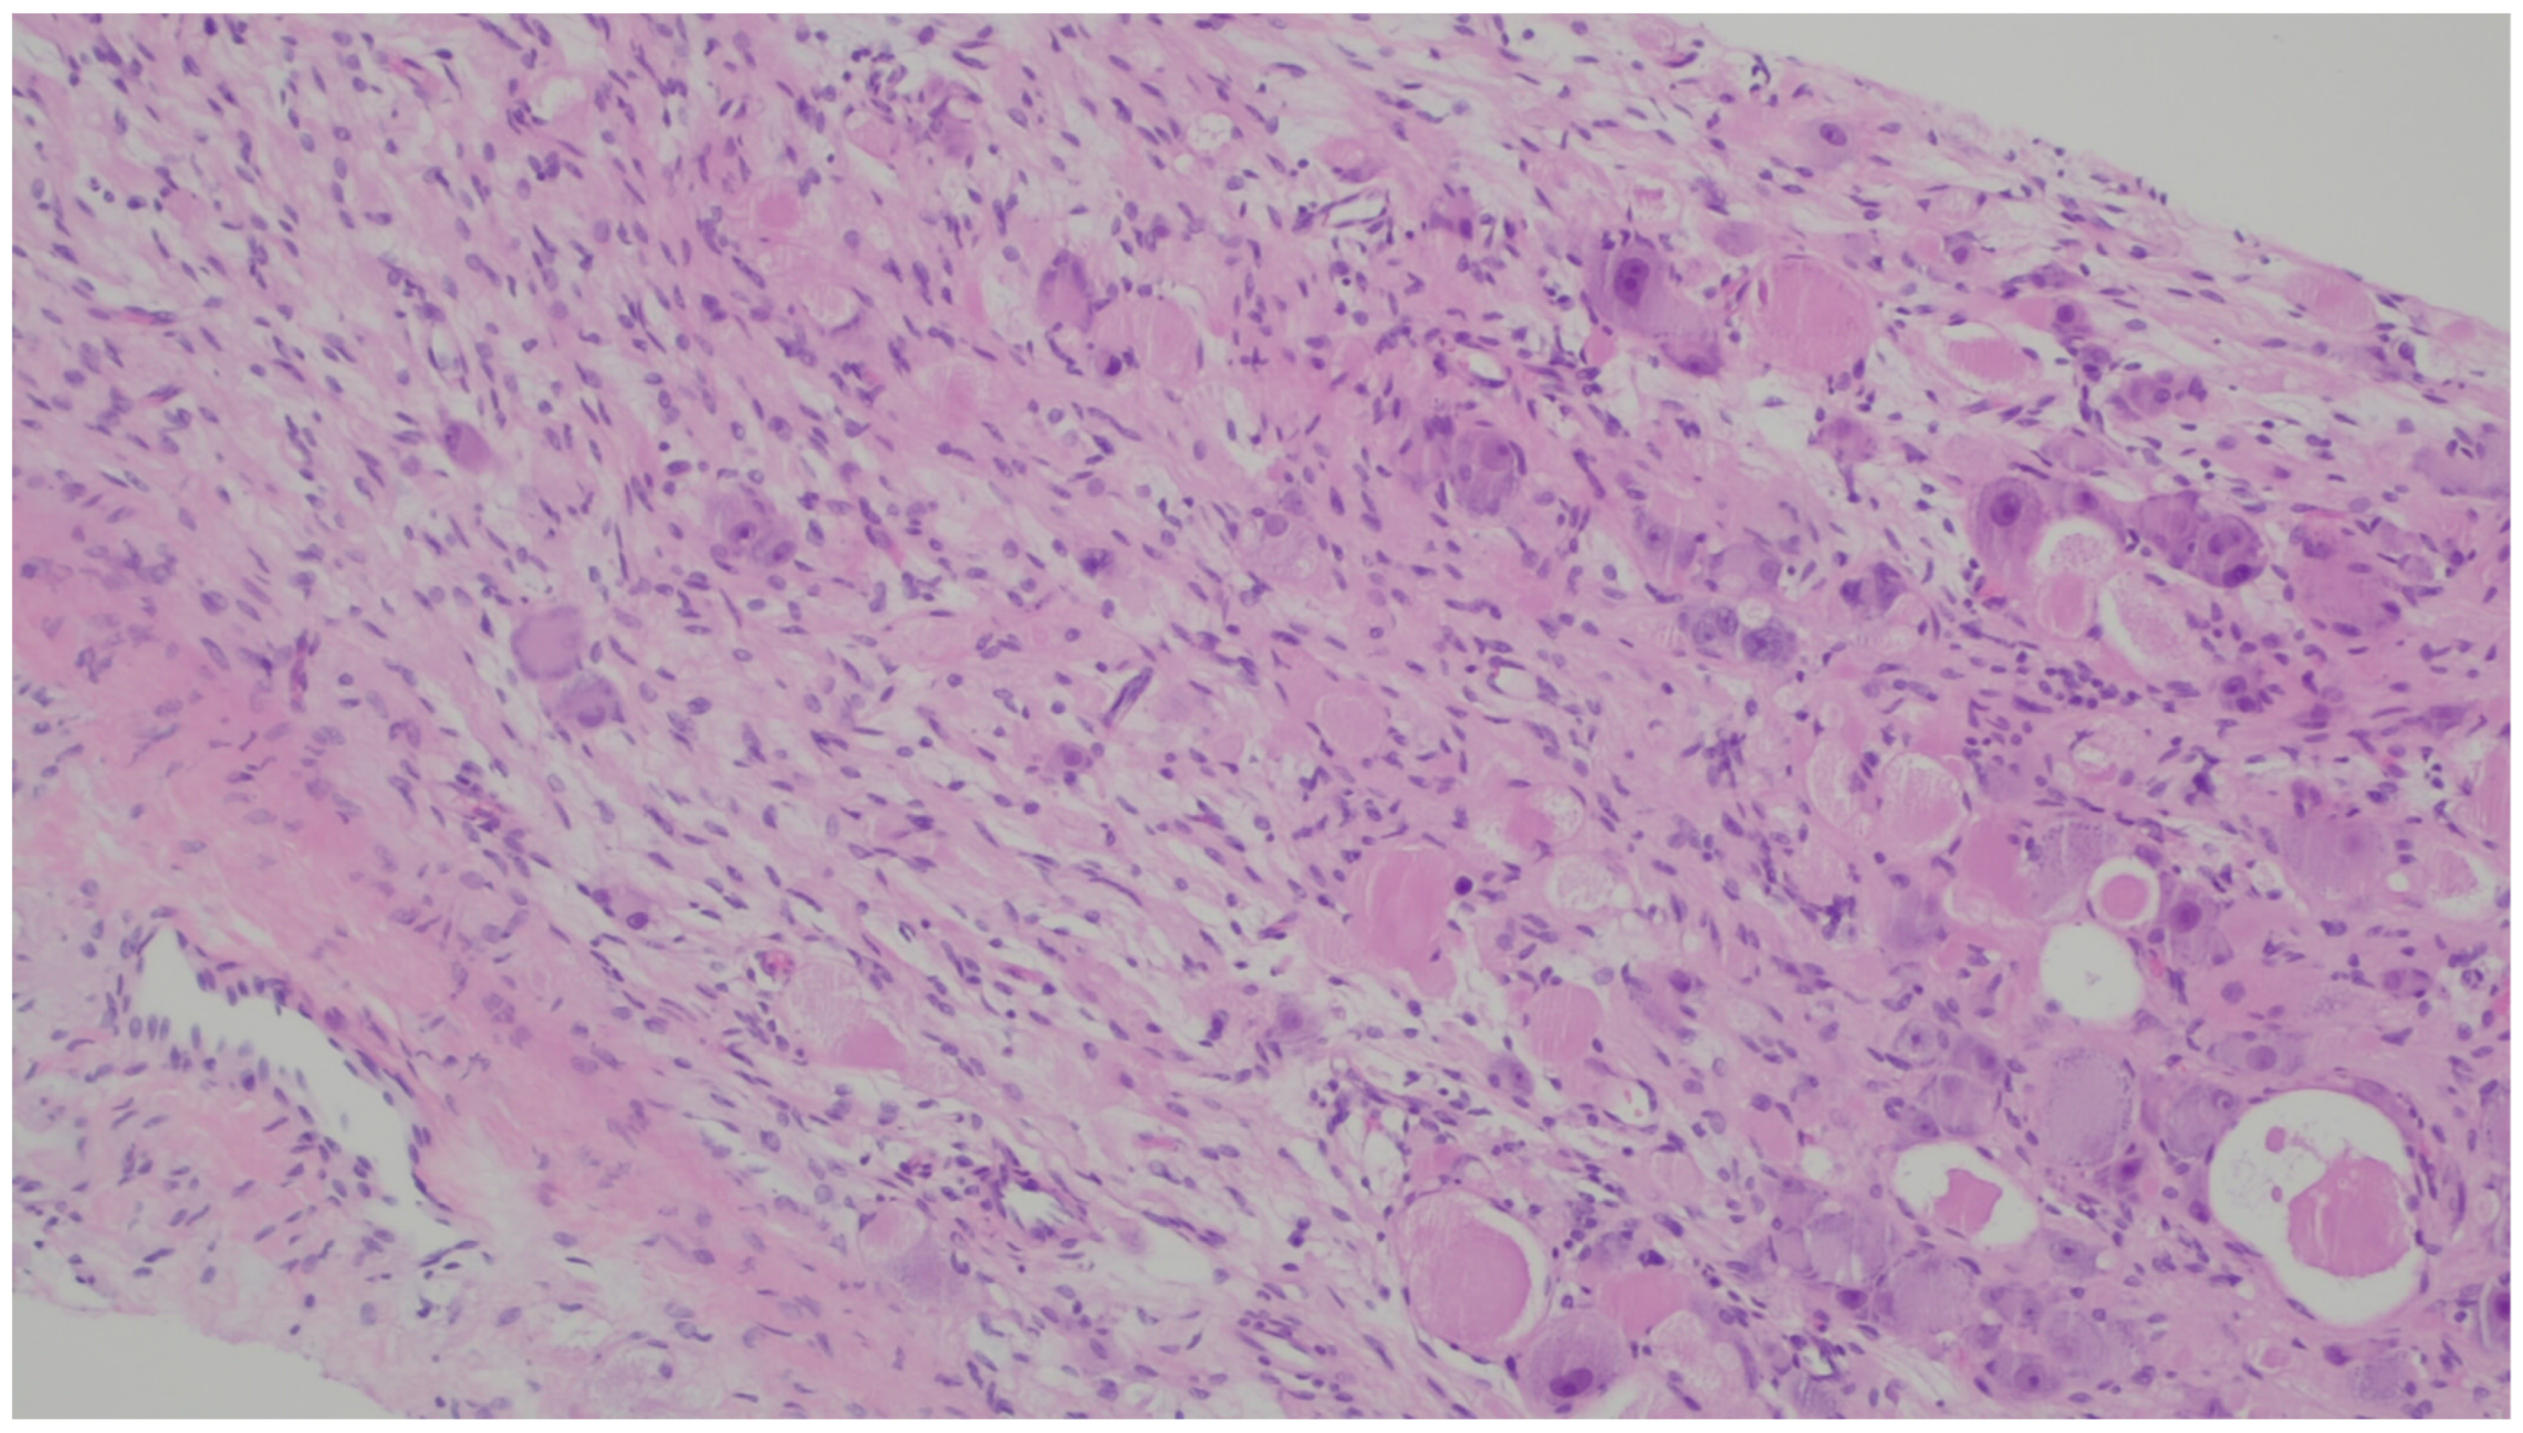

| NUTM1-rearranged colorectal sarcoma | Teens and young adults; more common in females | Colorectal | Symptoms are not specific | Three distinctive patterns: intersecting fascicles with uniform cells pattern, a hyalinized/nested pattern, and an epithelioid and rhabdoid pattern | nuclear expression of NUT, variable keratin expression and expression of CD117 and DOG1, retained expression of SMARCB1 and SMARCA4 |